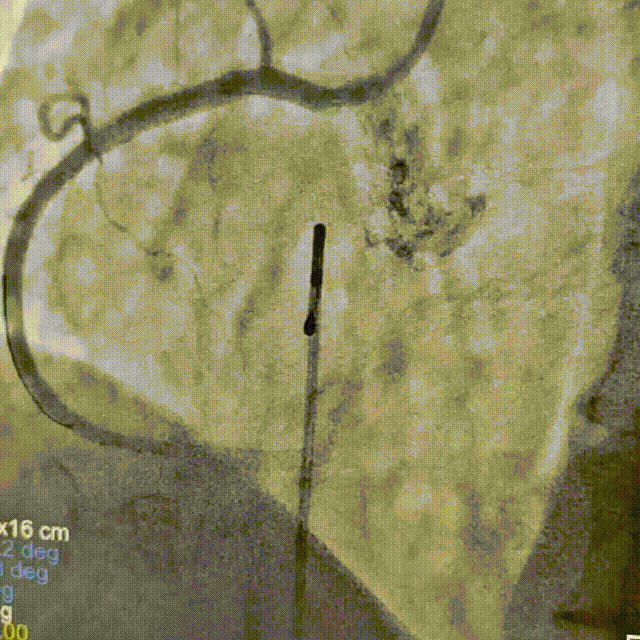

抽吸【例】量|抽吸新主【张】再论规范化操作